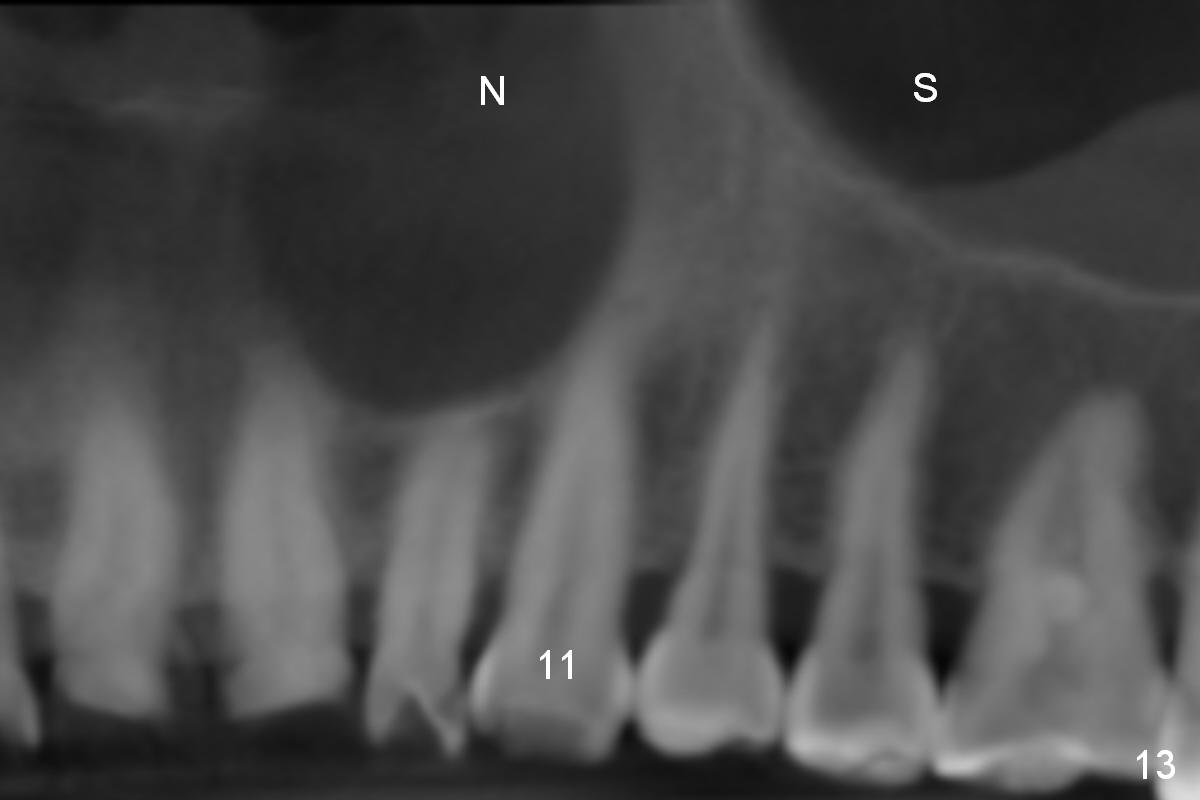

Eight months postop, the patient returns for #11 restoration. She reports no problem at #11, while there is light tenderness with a 2-piece implant (4.5x20 mm) at #6 at night (Fig.10, a portion of panoramic X-ray). Clinical exam reveals no abnormality at #6. Although the implant at #11 is buccally placed, there is no buccal plate atrophy (Fig.6,7). In fact the 20 mm 1-piece implant is placed in the bone (septum) between the nasal cavity (Fig.10 pink dashed line; Fig.13 (CBCT (52 year-old lady) N) and the maxillary sinus (yellow dashed line, S). In fact the apparent nasal floor indicated as arrowheads in Fig.2 and 10 is the horizontal plate of the palatine bone (hard palate)! Therefore there is no nasal floor perforation in this case. A long implant is indicated in the upper canine.